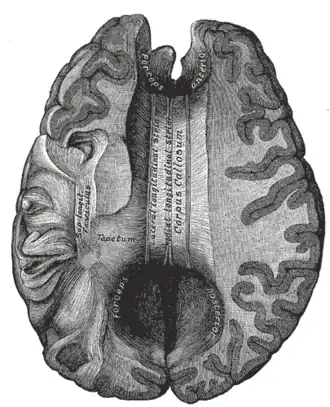

Corpus callosum from above, front part at the top of the image | |

The corpus callosum (Latin for "tough body"), also callosal commissure, is a wide, thick nerve tract, consisting of a flat bundle of commissural fibers, beneath the cerebral cortex in the brain. The corpus callosum is only found in placental mammals.[1] It spans part of the longitudinal fissure, connecting the left and right cerebral hemispheres, enabling communication between them. It is the largest white matter structure in the human brain, about 10 cm (3.9 in) in length and consisting of 200–300 million axonal projections.[2][3]

A number of separate nerve tracts, classed as subregions of the corpus callosum, connect different parts of the hemispheres. The main ones are known as the genu, the rostrum, the trunk or body, and the splenium.[4]

The corpus callosum forms the floor of the longitudinal fissure that separates the two cerebral hemispheres. Part of the corpus callosum forms the roof of the lateral ventricles.[5]

The corpus callosum has four main parts – individual nerve tracts that connect different parts of the hemispheres. These are the rostrum, the genu, the trunk or body, and the splenium.[4] Fibres from the trunk and the splenium, known together as the tapetum ("carpet"), form the roof of each lateral ventricle.[6]

The front part of the corpus callosum, towards the frontal lobes, is called the genu ("knee"). The genu curves downward and backward in front of the septum pellucidum, diminishing greatly in thickness. The lower, much thinner part is the rostrum and is connected below with the lamina terminalis, which stretches from the interventricular foramina to the recess at the base of the optic stalk. The rostrum is named for its resemblance to a bird's beak.

The end part of the corpus callosum, towards the cerebellum, is called the splenium. This is the thickest part, and overlaps the tela choroidea of the third ventricle and the midbrain, and ends in a thick, convex, free border. Splenium translates as "bandage" in Greek.

The trunk of the corpus callosum lies between the splenium and the genu.